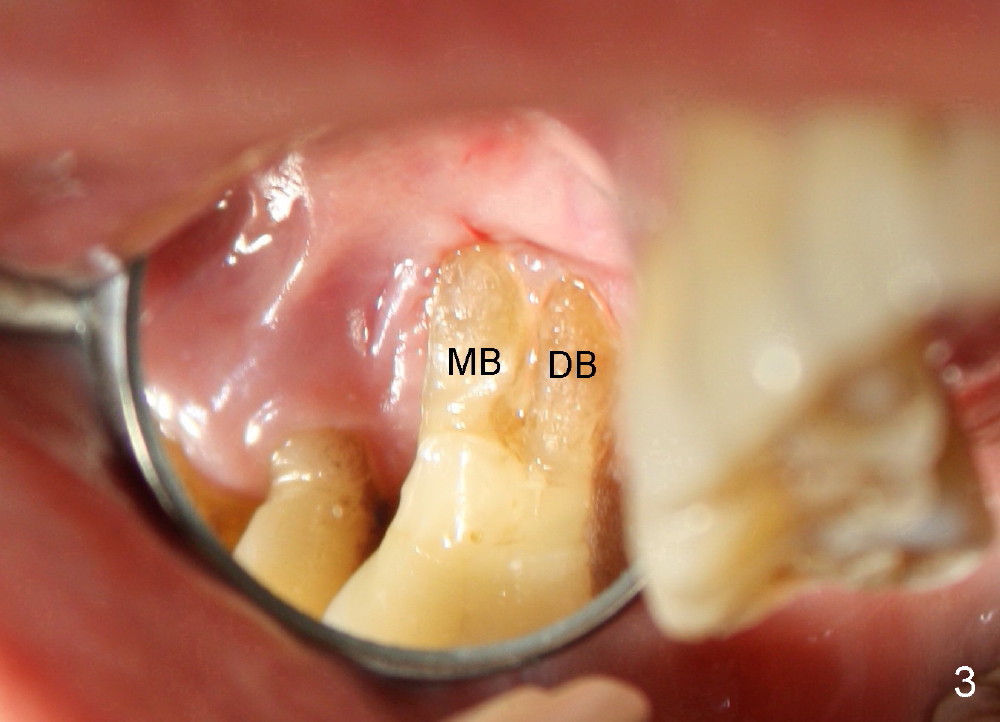

A 68-year-old lady presents to clinic with chief complaint of upper right pain. The tooth #3 has advanced periodontitis, compounded by occlusal trauma (Fig.1). There is severe bone loss, especially around the buccal roots, MB and DB. The latter are exposed (Fig.2,3).